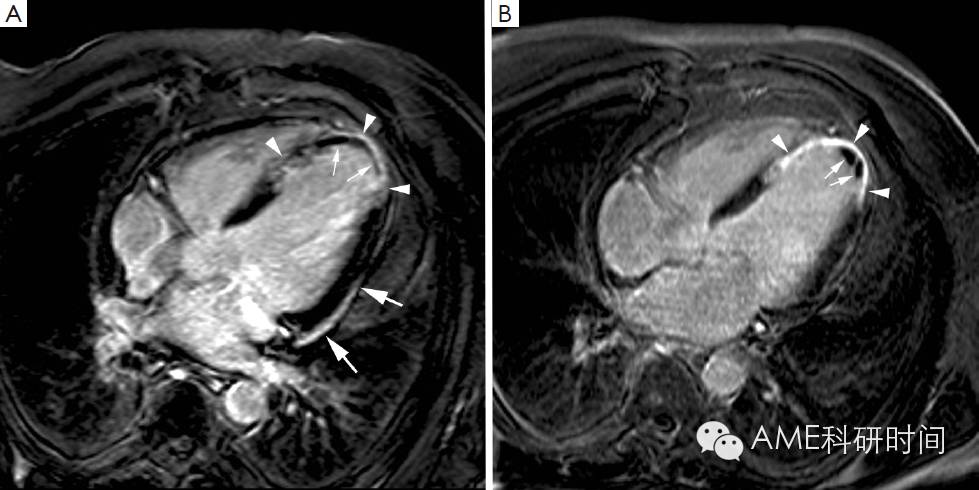

急性心肌梗死后,在坏死的心肌层位置出现一系列的病理生理变化,以坚硬的纤维瘢痕代替坏死的组织,同时为了维持相应的心脏输出,未梗死的心肌层出现代偿以弥补梗死的心肌层造成的损失。尸检结果表明在患者心肌梗死后坚硬的纤维瘢痕取代坏死的心肌的过程可能需要6周,此过程可能受再灌状态的影响(1)。纤维瘢痕替代坏死心肌的过程与受损区域的逐渐缩小有关,这有利于将受损区域最小化以及对抗梗死的血管壁的扩张。心脏LGE-MRI研究表明在急性心肌梗死发生到随访中期期间出现LGE区域持续减少。Ganame等(48)使用MRI对正在接受一级经皮冠状动脉介入治疗的ST段抬高的急性心肌梗死患者在缺血后早期、4个月和1年的状况进行研究。研究者证明在相比心肌梗死后早期,梗死后四个月的左心室体积减小约40%,然而缺血后1年体积没有进一步显著减小。因此这个结果证明了大多数心肌愈合出现在急性发病后的四个月内(图3)。在这个过程中,梗死周围(相邻)区域变薄并出现功能紊乱,这可能是由于受相邻区域坏死或纤维化的心肌的影响。然而,左心室的重塑持续至急性心肌梗死后1年,表现为远端非梗死的心室壁变薄,这至少部分与舒张末期心室壁应力增大,左心室体积增大以及左心室逐渐变成圆形结构有关(图6)。这些研究结果与目前公认的观点相左(即远端非梗死区域发生代偿性心肌肥厚),因此需要进一步的验证(49-52)。近来,我们也研究了梗死区位置和大小以及他们的相互关系是否影响梗死后心肌重塑(53)。在3个三甲医院,我们对正在接受经皮冠状动脉介入术治疗的,患有急性ST段抬高性心肌梗死的260名患者,在患病早期和4个月使用MRI进行研究。我们观察到由于受梗死位置的影响,前壁心肌坏死造成的负担更重,所以患有前壁心梗的患者在发病后左心室的重构和功能失调比下壁和侧壁心梗严重。Bogaert等(54)应用灵敏度高的心肌标记的心脏MRI检测心肌形状的改变,也发现在缺血后的早期远端非梗死心肌已经出现功能失调,对整个左心室的重塑和功能失调有显著影响,这可能是导致梗死区域纵向壁压力增大而没有减少内在的收缩性的原因。在Bogaert等(55)的另一项研究中,对患有透壁性前壁心肌梗死的患者在急性发病后1周和3周,使用心肌标记和晚期钆增强的心脏MRI进行研究。心肌标记的心脏MRI被用来对梗死区心壁中有活力的心外膜的边缘的变形程度进行局域性定量。他们在随访中观察到心外膜下纤维的缩短逐渐减少,这可能与对抗梗死区扩大和增加局部射血分数有关,有利于整个左心室的重构和功能恢复。因此,梗死心肌的愈合模式不仅影响梗死区域的重构和剩余的功能,而且对梗死区相邻和远程心肌的适应性反应产生影响,从而影响整个左心室的形状和功能。值得注意的是梗死区域缩小的程度随其位于梗死区域的方向,即径向、周向和纵向而非常不同。Fieno等(52)在犬再灌注心肌梗死的模型中,研究了梗死和非梗死区域的病程和形状变化。研究者发现径向梗死区域心室壁的厚度逐渐减小而周向和纵向梗死区域心室壁厚度的变化变异性大。心肌梗死径向区域容易被吸收与径向区域心室壁逐渐变薄有关,虽然有时为了对抗心室壁变薄和加速功能恢复而出现一定程度的心外膜肥厚。用实验方法也证明胶原纤维倾向于与坏死的心肌纤维平行分布,反应了心肌层的非均质性(56,57)。这种现象的产生是为了保护梗死心室壁的结构完整性,伴随产生了有抵御力和弹性的瘢痕沉积来抵抗心室的扩张,同时促进了梗死区域相邻心肌层的功能恢复。实验方法证明瘢痕的多样性使得瘢痕可以对抗心室变形导致的周向延伸,与纵向和径向相邻非梗死心肌相互协调(30,31)。连续全方位的MRI技术具有高空间分辨率,高信噪比和无创性的特质,可以描绘出梗死心肌和非梗死心肌复杂的重构过程以及他们对左心室扩张和功能失调的相对影响,为梗死后心室的重构提供独特的视角。

图6 Use of MRI for long-term follow-up of ventricular remodeling post myocardial infarction in a patient with an extensive anteroapical MI. Horizontal long-axis cine imaging at 1 week (A), 4 months (B), 1 year (C), and 5 years (D) after the acute event (end-diastolic time frames). Cine imaging allows to appreciate the infarct healing with thinning of the LV apex, and the progressive LV dilatation over time (A-D). The LV end-diastolic volumes at 1 week, 4 months, 1 year and 5 years are 167 mL, 180 mL, 230 mL, 257 mL respectively. Adapted from Ischemic Heart Disease by Bogaert J and Dymarkowski S, in Clinical Cardiac MRI Second Edition, Bogaert J, Dymarkowski S, Taylor AM, Muthurangu V (eds). Springer Heidelberg, Germany (ISBN 978-3-642-23034-9).